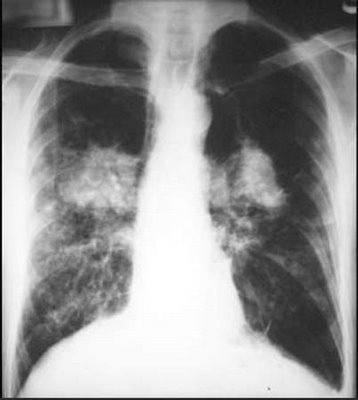

Рентгенологическая картина: распространенное усиление легочного рисунка за счет интерстициальных изменений. Легочный рисунок представляется тяжистым в случае преобладания перибронхиальных изменений или сетчатым при вовлечении в процесс периацинарных и перилобулярных элементов соединительной ткани. Корни легких расширены. При эмфизематозных изменениях обнаруживаются повышение прозрачности легочных полей, преимущественно в верхних отделах. В периоды обострений интерстициальные изменения нарастают, появляется сегментарная или полисегментарная пневмоническая инфильтрация.